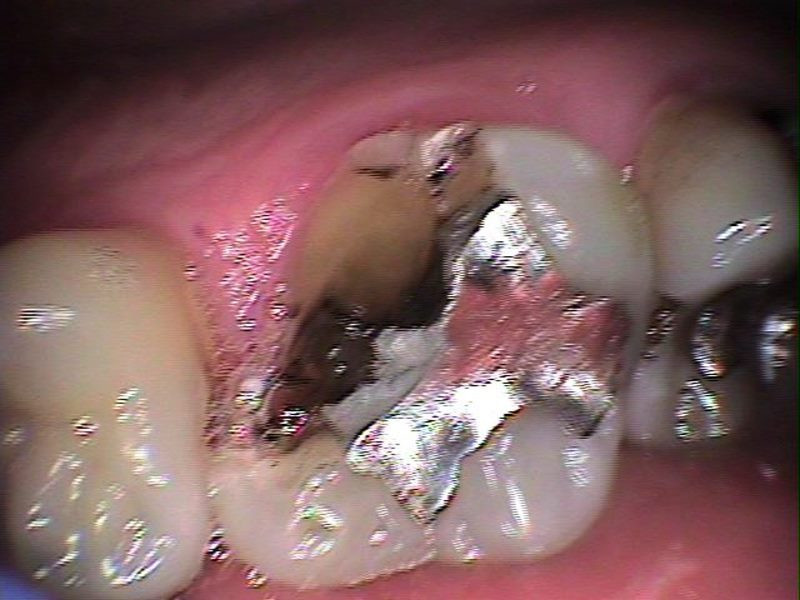

Antes